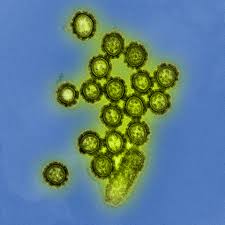

AKC just reported an alarming number of confirmed cases of canine influenza in dogs. This virus has a 2- 5-day incubation period. Signs include: fever, poor appetite, coughing, sneezing, runny eyes/noses. Two strains are now in 40 states (H3N8 and H3N2). The secretions escape into the environment by way of coughing, barking and sneezing, where they are inhaled by a new canine host. Dogs spread it through contaminated objects and the environment like water bowls, collars, kennel surfaces (walls, ceilings) or through contact with people who have had direct contact.

AKC just reported an alarming number of confirmed cases of canine influenza in dogs. This virus has a 2- 5-day incubation period. Signs include: fever, poor appetite, coughing, sneezing, runny eyes/noses. Two strains are now in 40 states (H3N8 and H3N2). The secretions escape into the environment by way of coughing, barking and sneezing, where they are inhaled by a new canine host. Dogs spread it through contaminated objects and the environment like water bowls, collars, kennel surfaces (walls, ceilings) or through contact with people who have had direct contact.